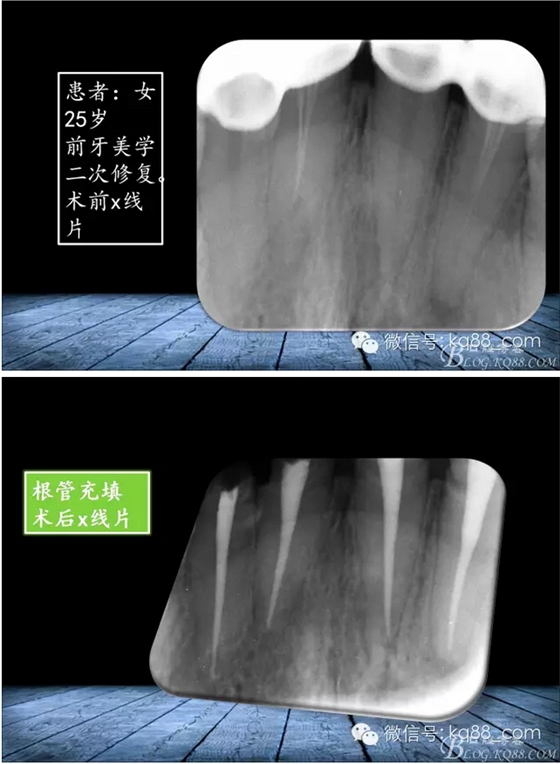

QQ圖片20150817140856.png

QQ圖片20150817140915.png